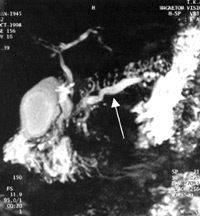

Ο κρυφός κόσμος του λεπτού εντέρου και τα προβλήματα που απορρέουν απ' αυτόν

ήρθαν στο φως με τη χρήση της εντεροσκόπησης με κάμερα. Η μέθοδος αυτή μπορεί

να χρησιμοποιηθεί και σε παιδιά μεγαλύτερα των επτά ετών (εικόνα 12).

Μια μικρή κάψουλα (κάμερα) έχει διαστάσεις 11x27mm και ζυγίζει 3.5γρ. Έχει την

ικανότητα φωτογραφικής απεικόνισης του τοιχώματος του λεπτού εντέρου με συχνότητα

δύο εικόνες ανά δευτερόλεπτο. Η συνολική διάρκεια καταγραφής είναι 6-8 ώρες.

Οι κυριότερες ενδείξεις για τη χρήση της μεθόδου είναι η διερεύνηση χρόνιας

ή διαλείπουσας αιμορραγίας, η διάγνωση νόσου Crohn, συνδρόμων δυσαπορρόφησης

(κοιλιοκάκη), ο εντοπισμός καλοήθων ή κακοήθων όγκων, η διάγνωση των βλαβών

του λεπτού εντέρου σε ασθενείς με HIV λοίμωξη.

Η διαγνωστική της ακρίβεια υπερβαίνει το 75%, η ευαισθησία και η θετική προγνωστική

αξία το 96% και το 92% αντίστοιχα. Φαίνεται ότι με τη μέθοδο αυτή, όλο και λιγότεροι

ασθενείς με παθήσεις του λεπτού εντέρου θα μένουν αδιάγνωστοι (εικόνες 13, 14).

ΕIKONA 13. Εντεροσκόπηση με μικροκάμερα.

ΕIKONA 14. Χαρακτηριστικές εικόνες μετά από εντεροσκόπηση με μικροκάμερα.